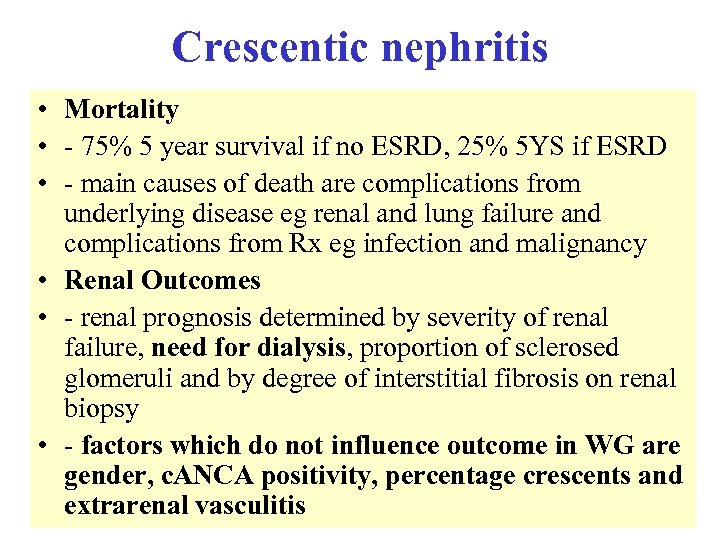

Crescentic nephritis • Mortality • - 75% 5 year survival if no ESRD, 25% 5 YS if ESRD • - main causes of death are complications from underlying disease eg renal and lung failure and complications from Rx eg infection and malignancy • Renal Outcomes • - renal prognosis determined by severity of renal failure, need for dialysis, proportion of sclerosed glomeruli and by degree of interstitial fibrosis on renal biopsy • - factors which do not influence outcome in WG are gender, c. ANCA positivity, percentage crescents and extrarenal vasculitis

Crescentic nephritis • Mortality • - 75% 5 year survival if no ESRD, 25% 5 YS if ESRD • - main causes of death are complications from underlying disease eg renal and lung failure and complications from Rx eg infection and malignancy • Renal Outcomes • - renal prognosis determined by severity of renal failure, need for dialysis, proportion of sclerosed glomeruli and by degree of interstitial fibrosis on renal biopsy • - factors which do not influence outcome in WG are gender, c. ANCA positivity, percentage crescents and extrarenal vasculitis